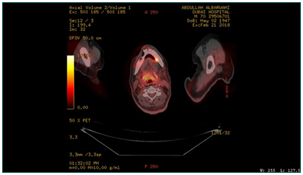

A 70 years old male patient presented to the emergency department with stridor and dysphagia of 3months duration. Patient was examined by fiber optic nasopharyngoscope which revealed supra-glottic mass to the left side with restricted mobility of the left vocal cord. Patient was admitted and submitted for urgent tracheostomy. MRI neck with contrast was done and revealed a Supraglottic mass measuring about 2cm X 1.5cm, partially occluding the airway and showing enhancement post gadolinium injection. It is appearing isointense in T1 and T2-weighted images with mildly enlarged vocal cords (Figure 1–3).  Panendoscopy was performed on 18/02/2018 and revealed a mass occupying the post cricoid area, pyriform fossa, supraglottic and the lateral pharyngeal wall. Base of the tongue, tonsils, right side of the larynx and the posterior pharyngeal wall were free.

Figure 1 MRI neck with contrast, axial cut showing supraglottic mass lesion partially occluding the airway.

Figure 2 MRI neck, axial cut, showing supraglottic mass lesion partially occluding the airway.

Figure 4 PET CT scan, showing hypermetabolic focus at the hypopharyx, post cricoid area.

Figure 5 PET CT scan, showing hypermetabolic focus at the region of left mandible, adjusting left margin of the tongue.

Figure 6 PET CT, showing hypermetabolic suspicious lymph node in the right infraclavicular region, hypermetabolic focus in the region of left mandible.